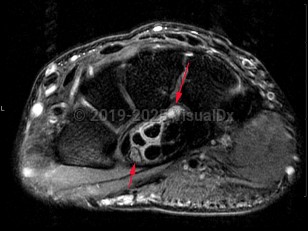

Imaging Studies image of Carpal tunnel syndrome - imageId=7899721. Click to open in gallery.  caption: '<span>Axial intermediate weighted  MRI sequence demonstrates inflammation surrounding the flexor tendons  within the carpal tunnel, with edema of the median nerve (shorter arrow).  Compatible with carpal tunnel syndrome.</span>'

Axial intermediate weighted MRI sequence demonstrates inflammation surrounding the flexor tendons within the carpal tunnel, with edema of the median nerve (shorter arrow).  Compatible with carpal tunnel syndrome.